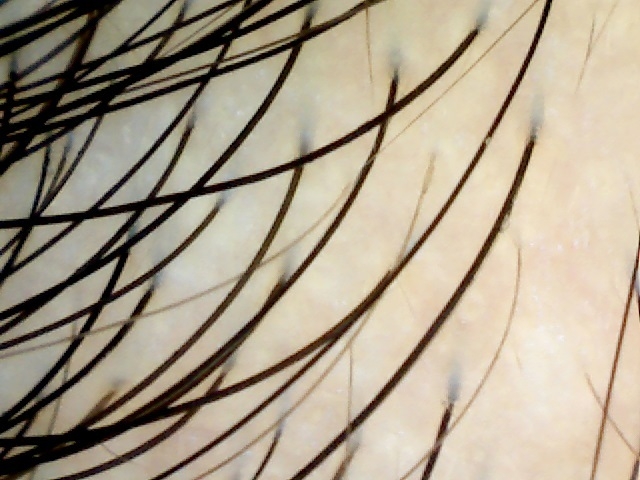

側頭部生え際のマイクロスコープ写真 Before(0ヶ月)

側頭部生え際のマイクロスコープ写真 After(3ヶ月)

使用前より使用開始3ヶ月後で、側頭部生え際の白髪および白髪の根元部分全体に色の濃化が認められた。